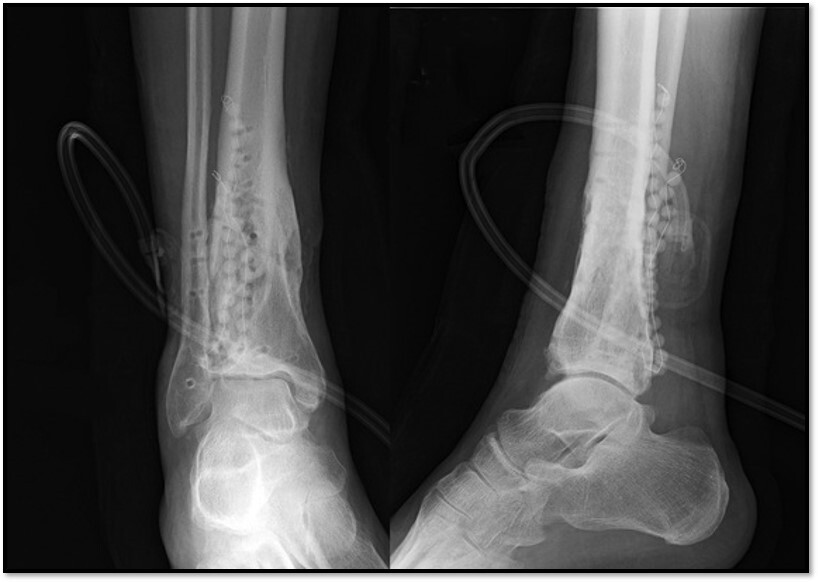

What is this showing here?

Antibiotic leads

How well did you know this?